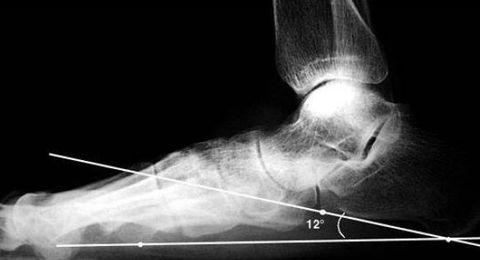

What is this angle called? What foot type does it indicate? | Talar - 1st MT or Meary's Angle Pes plano-valgus |